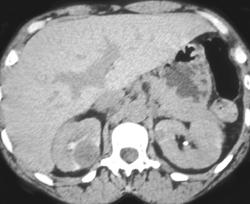

Bilateral Renal Metastases From Lung Cancer